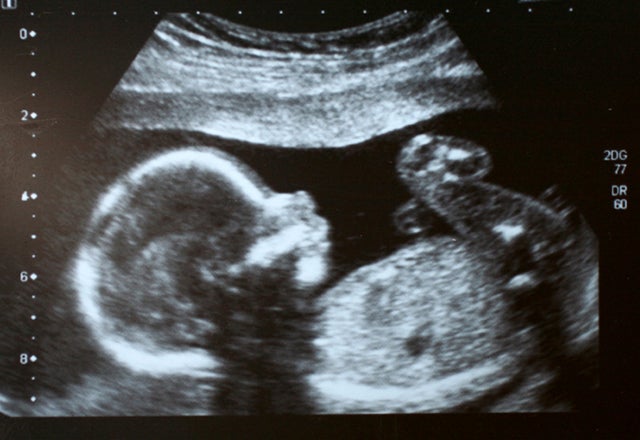

Sadly, unlike my friend going through a mammogram scare, many pregnant women today having prenatal screenings aren’t going through the full battery of tests to see if the “something” they are worried about – most often Down Syndrome or abnormalities that could cause the baby’s death shortly after birth – is actually reality.

The more parents can know about their unborn child in advance the better they can be prepared – whether it is something as trivial as having the nursery painted blue because they know it’s a boy or something far more serious such as a medical condition they can treat in advance or be better prepared for once the baby is born.